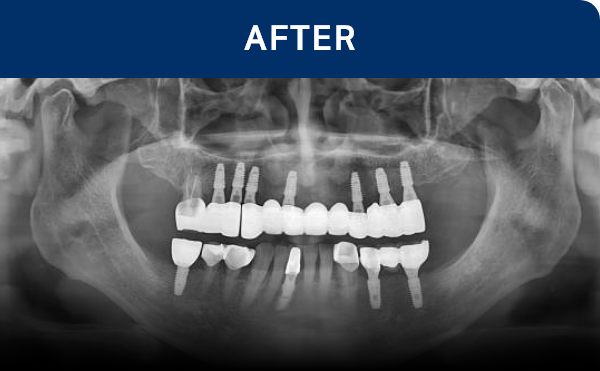

清晰可见的成果,

就是新吉种植牙

科值得信赖的证明.

通过种植牙, 让您无忧进食, 自在微笑, 重拾生活的舒适感